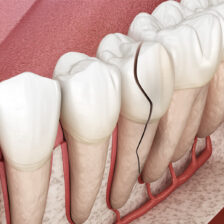

本当に根管治療が必要か?必要だとしてどの歯が原因なのか?

各種精密な診査を行い説明を行います。

また、根管治療によりどのくらいの成功率で残せるのか?

当院では世界的なエビデンスデータを用いながら当院オリジナルの治療実績も踏まえてご説明いたします。